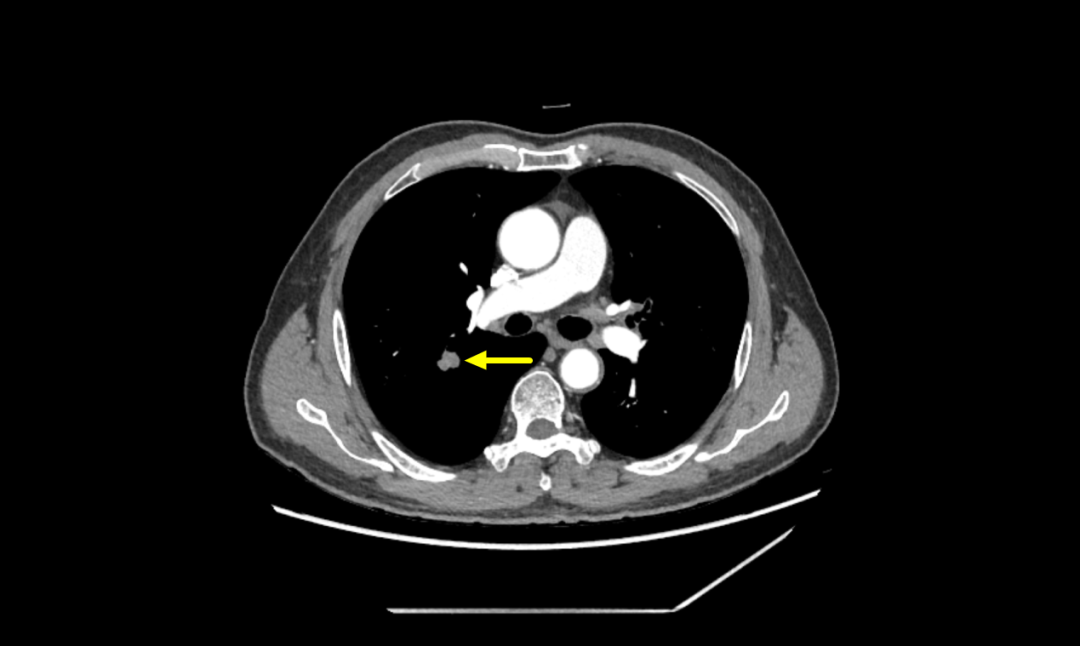

患者李伯,70岁,因“咳嗽、咳痰3月,发现肺部结节20天”入院。患者有慢性阻塞性肺病史,曾因膀胱结石行微创手术治疗,有30余年吸烟史。入院后查体发现双肺呼吸音低,胸部CT显示右肺上叶后段实性结节,有分叶、短毛刺,与血管相连,中度强化,考虑恶性可能性大。

▲胸部增强CT提示右肺结节,恶性可能性大